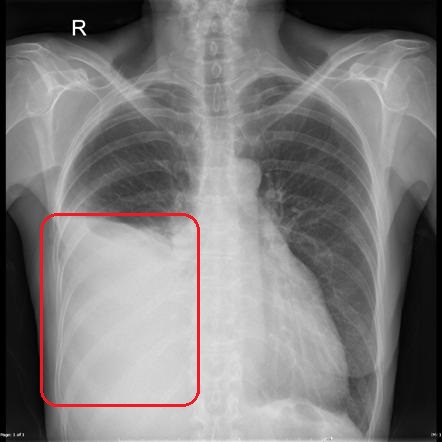

Рентгенография. Дает возможность определить наличие жидкости, если ее количество составляет от 300 — 400 мл. Также данный метод позволяет обнаружить опухолевые очаги и метастазы, которые распространились в плевральную область и лимфатические узлы. Рентгенографию осуществляют и для контроля состояния пациента после процедуры эвакуации (удаления) жидкости из легких.

При проведении визуального осмотра пациента врач обращает особое внимание на поражённую половину грудной клетки, которая явно отстает при дыхании. При выстукивании врач обнаруживает в нижних отделах грудной клетки существенное укорочение звука, а в поражённой зоне полное отсутствие шумов дыхания. Обследуя грудную клетку методом рутинной рентгенографии можно с легкостью выявить классические признаки плеврита.